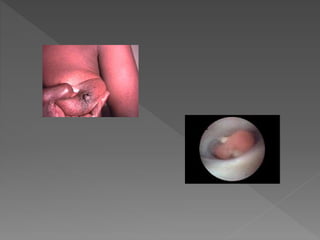

 MASA MAMARIA

 DESCARGA SANGUINOLENTA

 ENFERMEDAD DE PAGET

Dr. S. Ralon